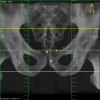

Over the last decade, BMC Cancer has continuously published important research from the field of radiation oncology. Major developments in this field include the introduction of new imaging modalities into radiotherapy planning, the availability of hardware and software for more precise delivery of radiation dose, the individualization of radiotherapy concepts, for example, based on microarray data, and the combination of radiotherapy with molecular targeting approaches to overcome the radioresistance of tumor cells.